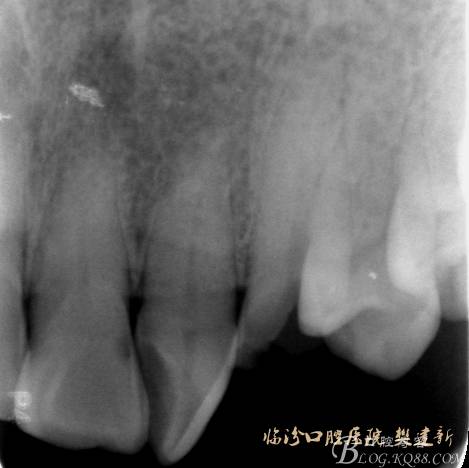

口內(nèi)檢查: 23殘根,位于齦上3MM,根管口探無反應(yīng),叩(+-),無松動,牙周無紅腫.X片示:23根管無阻射,根尖骨密度降低.11.12.13頸部楔形缺損,探敏感,牙髓活力正常.全口牙結(jié)石色素(+).

圖2 治療前X片: 23殘根,根尖區(qū)骨密度降低.

圖3 根管治療后X片